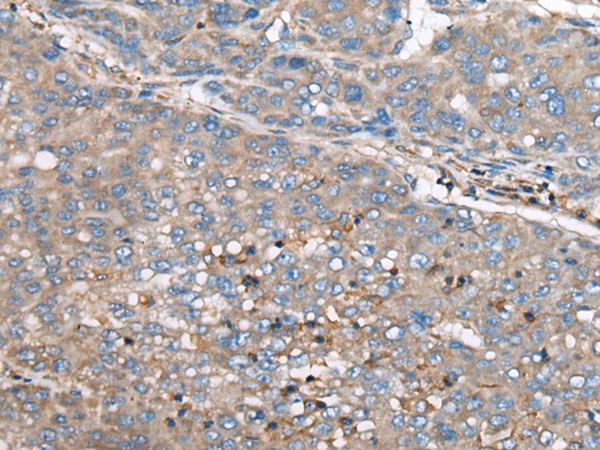

The image on the left is immunohistochemistry of paraffin-embedded Human liver cancer tissue using 46570(GULP1 Antibody) at dilution 1/65, on the right is treated with synthetic peptide. (Original magnification: x200)